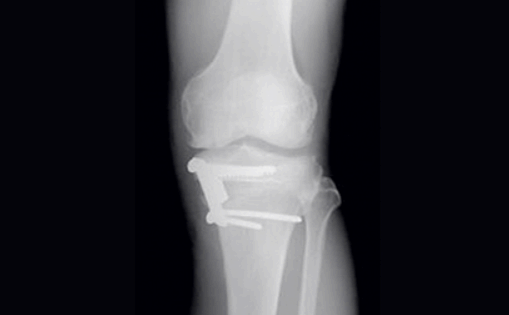

이 밖에도 뼈와 연골 일부를 제거하고 인공관절을 삽입하는 수술로 통증이 심해 일상생활이 불편하신 분들에게 적당한 인공관절치환술이 있고, 연골판 양쪽을 십자 형태로 봉합하는 십자봉합술이 있습니다. 이는 정상 모양과 유사하도록 안착시켜 주는 방식으로 강도를 높여주고 있습니다.

무릎 연골 손상 수술비용 한쪽 무릎만 수술할 때 그리고 양쪽을 다 수술할 때 당연히 그 비용이 달라지는데요. 한쪽만 하는 경우에는 보통 200만 원에서 300만 원 사이, 양쪽을 모두 수술할 때에는 400만 원에서 500만 원 사이의 수술비용이 필요합니다.

어떠한 방법으로 수술을 진행하느냐에 따라서 물론 달라지고 병원마다 장비가 다르기 때문에 무릎 연골 손상 수술비용 어느 정도는 차이가 있을 수 있으나 보통은 거의 위의 비용 사이에서 가능합니다.

간혹 상황이 정말 심각한 경우에는 500만 원 이상의 수술비용이 필요할 수 있으니 정확한 것은 전문의와 상담하시면 아실 수 있습니다. 무릎 연골 손상 수술은 절대 간단한 수술이 아니기 때문에 그만큼 전문의의 경험이 절대적으로 중요합니다. 너무 수술비용에 치중하기보다는 경험이 풍부하고 후기가 좋은 곳을 여러 곳 비교해서 병원을 정하시기를 바랍니다.